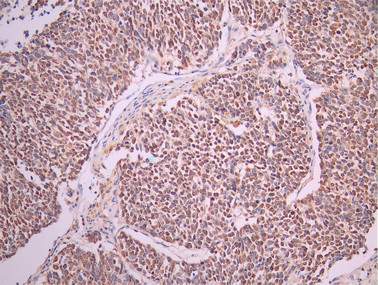

IHC image of CSB-RA449123A0HU diluted at 1:100 and staining in paraffin-embedded human lung cancer performed on a Leica BondTM system. After dewaxing and hydration, antigen retrieval was mediated by high pressure in a citrate buffer (pH 6.0). Section was blocked with 10% normal goat serum 30min at RT. Then primary antibody (1% BSA) was incubated at 4°C overnight. The primary is detected by a Goat anti-rabbit polymer IgG labeled by HRP and visualized using 0.05% DAB.